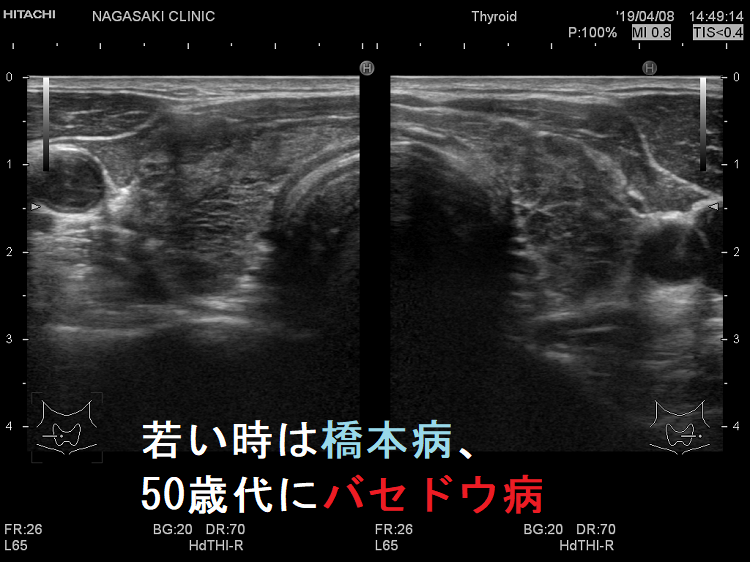

よくあるパターンは「若い時、バセドウ。齢(とし)いって橋本」と言うやつです。(当然、逆もあり)

Th1優位になれば橋本病、Th2優位になればバセドウ病になります。同一人物でもTh1/Th2バランスが変われば、橋本病とバセドウ病が入れ替わるのです。